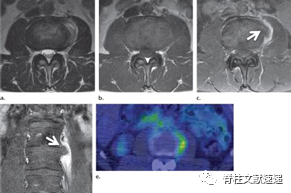

图注:硬膜内腰椎间盘突出

图注:42岁男性,有L4/5椎间盘切除手术史,出现急性马尾综合征。术中见硬脑膜上有小开口,硬膜内部分钙化椎间盘组织。

1942年Dandy首次描述了硬膜内腰椎间盘突出症,椎间盘组织延伸至硬膜内。

不到1%的腰椎间盘突出症发生在硬膜内。L4/5最常见。在胸椎,大多数发生在T8-T11。病变组织往往很大。椎间盘突出穿过纤维环、后纵韧带和硬脑膜。

在MR轴位T2加权图像上可有“鹰嘴”征。典型的慢性症状;马尾综合征常见;在颈部和胸部,Brown-Séquard综合征或严重脊髓病的发病率很高。

图注:49岁男性,极外侧腰椎间盘突出症,有黑色素瘤病史。(e) 轴位PET图像显示病灶部位有FDG摄取,怀疑黑色素瘤转移。经过3周的保守治疗,病人的病情有所好转。临床上并没有黑色素瘤诊断。